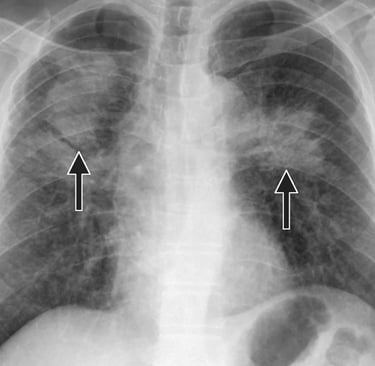

Jednym z najświeższych dokumentów jest raport „Effects of Welding on Health 2023” opracowany przez AWS i inne ośrodki — w którym zauważono między innymi, że spawacze wykazują obniżoną funkcję oddechową, a stężenia tlenków chromu (Cr VI) i manganu są podwyższone w środowisku pracy. Link: aws-p-001-delivery.sitecorecontenthub.cloud

W praktyce oznacza to, że choć czujesz się „w porządku”, Twoje płuca mogą już pracować z gorszą efektywnością — szczególnie jeśli spawasz codziennie, przez lata.

Inne badania wskazują, że nawet klasyczne testy spirometryczne mogą nie wychwycić wczesnych zmian — nowe metody, jak oscylometria czy biomarkery krwi (np. markery zapalne), wykazują subtelne uszkodzenia u osób, które klasycznie „mieściły się w normie”. aws-p-001-delivery.sitecorecontenthub.cloud

Badania wskazują, że w spawalnictwie są ekspozycje na lotne związki organiczne (VOCs) i ultradrobne cząstki, które mogą przenikać głęboko do płuc — a współczynnik stanów zapalnych może rosnąć. Link: aws-p-001-delivery.sitecorecontenthub.cloud

Istnieje także związane ryzyko zwiększonej podatności na zakażenia pneumokokowe u spawaczy — z kilku analiz wynika, że choroby układu oddechowego częściej dotykają osoby, które pracują z metalami spawalniczymi. Link: aws-p-001-delivery.sitecorecontenthub.cloud